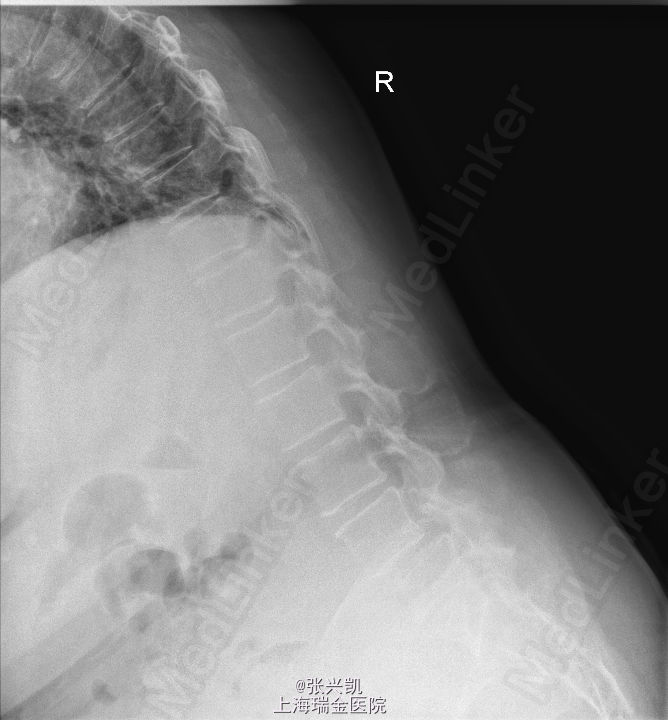

主诉:腰痛伴下肢疼痛3年余,近期双下肢疼痛加重 现病史:患者10年前出现腰痛,症状可自行缓解,未予重视,3年前出现腰痛伴双下肢疼痛,右侧为重,3个月来无明显诱因,症状加重,患者因腿痛无法正常行走,需借助一定器械、外物,弯腰前倾行走。

查体:脊柱无侧弯畸形,无叩痛压痛,上肢感觉肌力正常,双下肢疼痛,右侧较重,小腿前外侧感觉异常,下肢肌力4-5级,跟膝腱反射(+),巴氏征(-) 辅助检查:X线动力位示:L4椎体滑脱,腰椎退行性改变 MR:L4椎体向前I°滑脱,L3-5椎间盘突出,椎管狭窄

诊断:腰椎椎管狭窄L4-5 L4椎体滑脱 处理:腰椎后路减压复位融合内定术